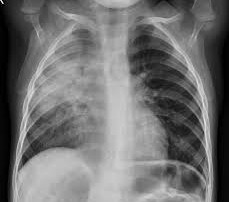

Neumonía en pediatría

La neumonía pediátrica representa una de las principales causas de morbilidad y mortalidad infantil a nivel global, siendo responsable de un alto número de consultas en los servicios de urgencias y hospitalizaciones cada año. Es fundamental establecer la diferencia entre la neumonía adquirida en la comunidad, que es aquella infección pulmonar que afecta a un niño que no ha estado ingresado en un centro hospitalario […]